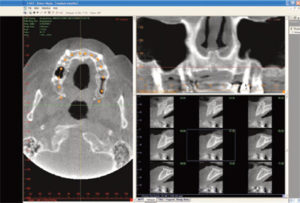

Time and again, 3-D's precision imaging reveals what 2-D X-rays never could: The true interrelationships between positions, shapes, and measurements of every facial feature. It's a dynamic connection simply impossible to pinpoint with 2-D X-rays.

Moreover, combining the power of a 3-D radiographic image with a highly precise color 3-D surface image creates anatomicallyaccurate 3-D replications of patients' faces for diagnosis.

Having a Cone Beam CT system in-office directly influences a practice's overall quality of care. Creating a "virtual patient" gives practitioners the most complete information on the anatomy of a patient's mouth, face, and jaw areas, and leads to the most accurate treatment and predictable outcomes for patients' surgical procedures.